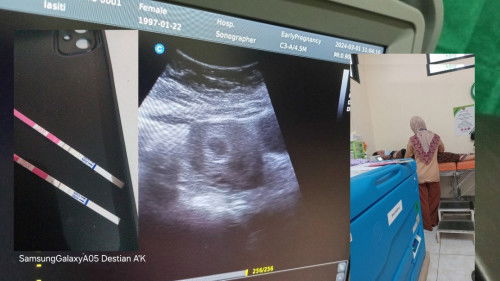

4minggu baru seperti ini apa wajar bun

4 minggu baru kantong apa wajar bun

soalnya prnh hamil kosong jadi takut seperti itu lagi bun jadi takut

wajar bun, janin terlihat umumnya di 7minggu